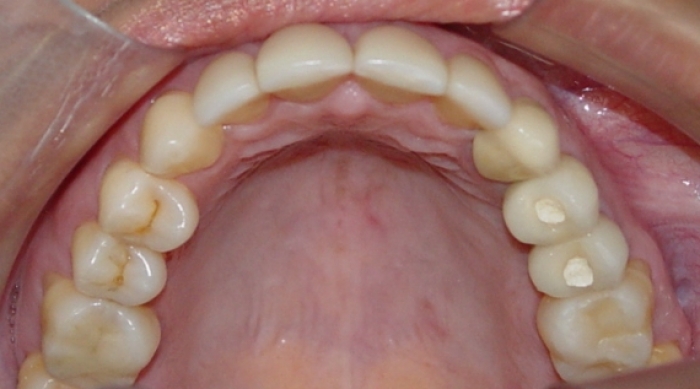

Próteses fixas de porcelana instaladas

Imagem e sorriso final do caso terminado em junho de 2011